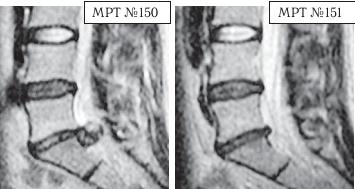

На МРТ № 152 наблюдается секвестрированная грыжа межпозвонкового диска в сегменте LV-SI. На МРТ № 153 наблюдается состояние поясничного отдела позвоночника после одного курса лечения методом вертеброревитологии. Многолетние наблюдения показали, что когда усилиями врача и пациента создаются идеальные условия для регенерации повреждённых дегенеративно-дистрофическим процессом межпозвонковых дисков и в период реабилитации с данным пациентом не происходят, например, случаи травматизации и «срывов», вследствие чрезмерной физической нагрузки, то выстраиваемая, благодаря методу вертеброревитологии, биомеханическая конструкция после последнего сеанса может держаться фактически год, — то есть весь продолжительный период постепенной регенерации вплоть до полной реституции межпозвонкового диска. Это подтверждено результатами МРТ-снимков, в том числе пациентов, живущих в дальнем зарубежье и не имеющих возможности по тем или иным причинам приезжать ко мне в клинику вертеброревитологии на контрольные сеансы. Однако контакт с пациентами не прерывается, что обеспечивает возможность отслеживать состояние их позвоночника в течение длительного периода времени. Приведу ещё пример, связанный с результатами лечения методом вертеброревитологии.